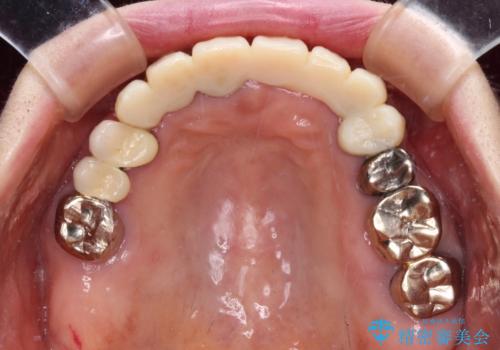

処置を予定していた歯を仮歯に変えた時点で、下顎前歯の部分矯正を行うかどうかを尋ねたところ、折角なので行いたいと言うことでしたので、矯正治療を行うこととしました。

インプラント埋入や根管治療治療など、治癒に一定の期間を要する処置の合間に矯正治療を行うことで、効率的に治療を進めて行くことができました。